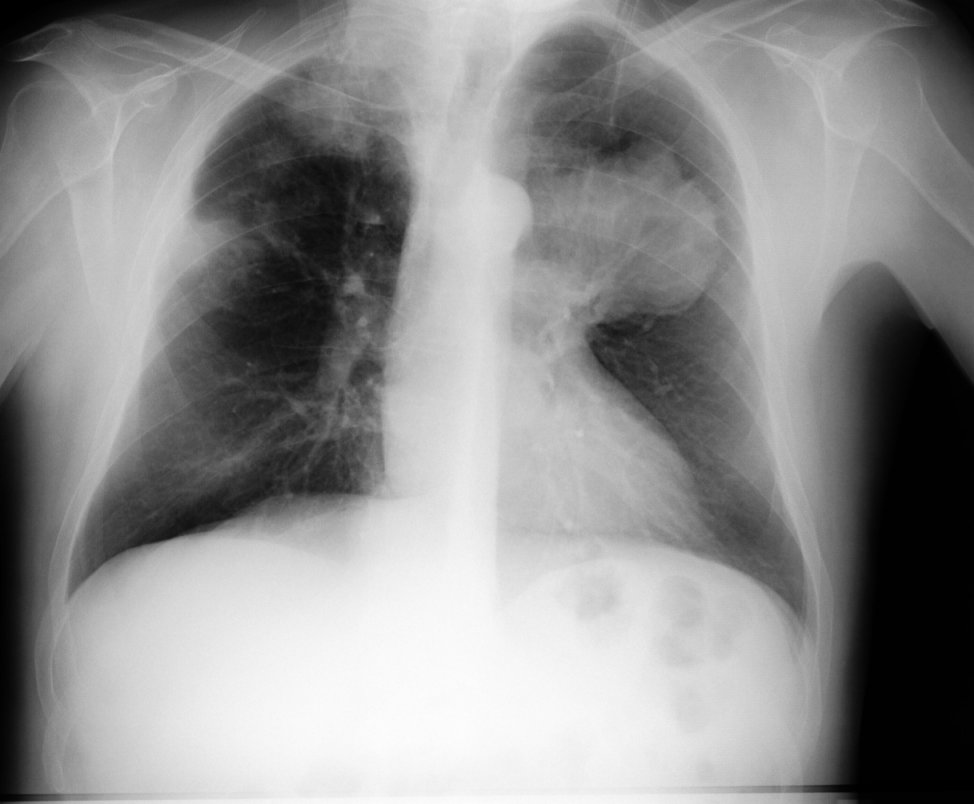

Citar como: Amorín Kajatt E. Cáncer de pulmón, una revisión sobre el conocimiento actual, métodos diagnósticos y perspectivas terapéuticas. Rev Peru Med. Presentamos 9 pacientes con diagnóstico sincrónico de tuberculosis pulmonar activa y carcinoma broncogénico en un período de S años. Todos eran varones. Developing an effective treatment plan for lung cancer involves input from a variety of specialists. For many patients, the time from diagnosis to the start of.

Journal of Thoracic and Cardiovascular Surgery British Medical Journal Photochem and Photobiol La tasa de mortalidad en fue de The objective of this consensus is to guide health personnel on the steps to follow for the timely diagnosis of the solitary pulmonary nodule and the disease with frank characteristics of malignancy Locally advanced and metastatic for its early reference to the Multidisciplinary Management group.

The different diagnostic methods are mentioned, being also explained the new technologies used for the diagnosis. Entre ellos, se han desarrollado los denominados life system y safe system 17, Cuba e-mail alinamc finlay. Abstract In all patients with suspected lung cancer, obtaining tissue for pathological analysis is of vital importance prior to the initiation of any treatment. Ann Intern Med ; Archivado del original el 18 d’ochobre de Bulletin of the World Health Organization64 3: Department of Health and Human Services.